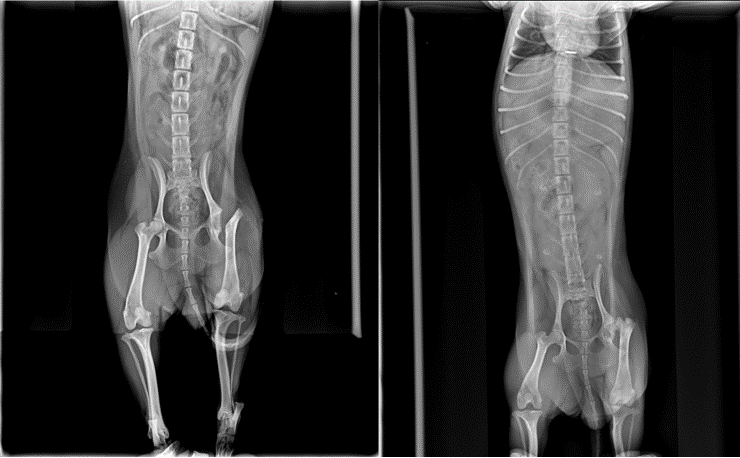

這天,主人帶著10個月大的約克夏幼犬『水水』來看診!一進門就看出跛腳的症狀,獸醫師看出『水水』不願用後腳走路,在拉伸左後腳時,髖關節發出骨頭的摩擦聲,其實在就診前,已經跛腳兩星期了。啄木鳥動物醫院馬上用X光檢查,發現股骨頭已經變型,而且股骨頸斷裂、骨折;果然是缺血導致的『壞死性髖關節炎』症狀。其實早在九月大時,就診斷出有潛在的發病危機。

啄木鳥動物醫院X光檢查,發現股骨頭不再圓滑、密度明顯偏低!

台南『啄木鳥動物醫院』用X光,發現股骨頭表面粗糙、不再圓滑,而且密度明顯偏低,很明顯是骨頭缺血所造成的!供應股骨頭營養來源有兩條血管,不論是先天性發育不良、或後天性創傷壓迫,導致血管閉塞,都是骨頭缺血的主因。這時候,手術幾乎是唯一的治療方法,必須切除股骨頭、及股骨頸,壞死的部分全部都要切除乾淨,目的就是要減少股骨頭關節間的摩擦。